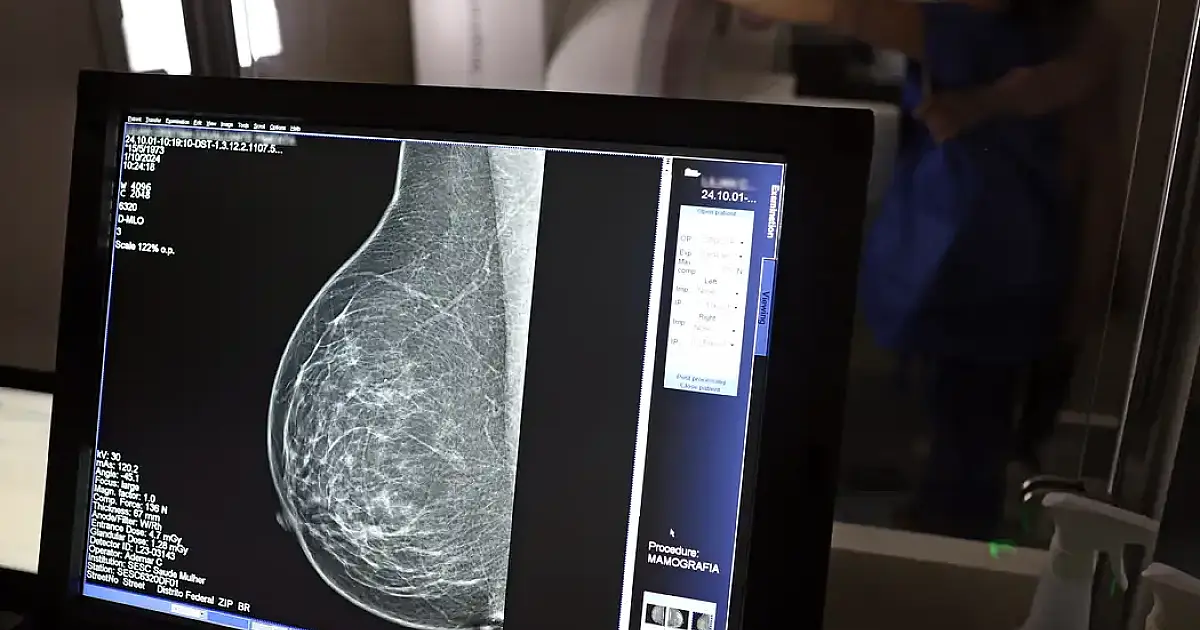

O Ministério da Saúde passou a recomendar o acesso a mamografia, via Sistema Único de Saúde (SUS), para mulheres de 40 a 49 anos – mesmo que não haja sinais ou sintomas de câncer de mama. De acordo com a pasta, a faixa etária concentra 23% dos casos da doença, e a detecção precoce aumenta as chances de cura.

Até então, a orientação era que o exame fosse feito a partir dos 50 anos.

As mamografias via SUS em pacientes com menos de 50 anos, de acordo com a pasta, representam 30% do total, o equivalente a mais de 1 milhão apenas no ano de 2024.